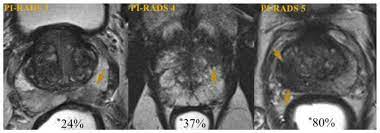

Likelihood Of Significant Prostate Cancer Detection By Mri Suspicion Download Scientific Diagram

Likelihood Of Significant Prostate Cancer Detection By Mri Suspicion Download Scientific Diagram from www.researchgate.net